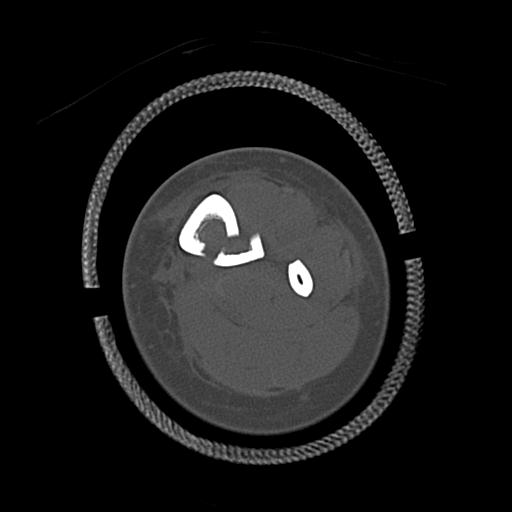

56476 8/28 4R 1/21 2R 左足関節 デジカメ写真 72歳女性 右足関節AS